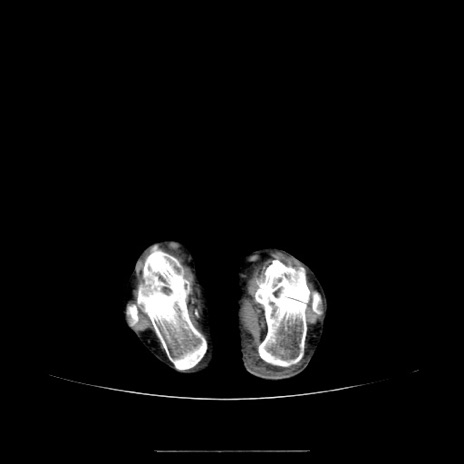

冠状断像

【症例】70歳代女性

【主訴】お腹が張る

【現病歴】1週間くらい前から腹部膨満の自覚あり。昨日夜から増悪したため、本日救急外来受診。

【身体所見】意識清明、BT 36.5℃、BP 165/106mmHg、HR 80bpm、SpO2 98%、腹部:膨満、軟、自発痛・圧痛なし、触診にて不快感あり、腸蠕動音:減弱

【データ】WBC 12600、CRP 1.04